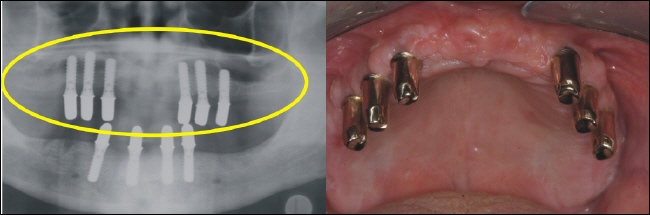

Die fertige Arbeit ermöglicht auf den sechs Teleskopen im Oberkiefer eine rein kieferkammbegrenzte, also gaumenfreie Versorgung. Das Röntgenbild links zeigt die solide Konstruktion, die eine reine Kaukraftweiterleitung in den Kieferknochen ermöglicht. |

Auch im Unterkiefer ist der Zahnersatz auf den Kieferkamm begrenzt und ermöglicht so höchsten Tragekomfort. |